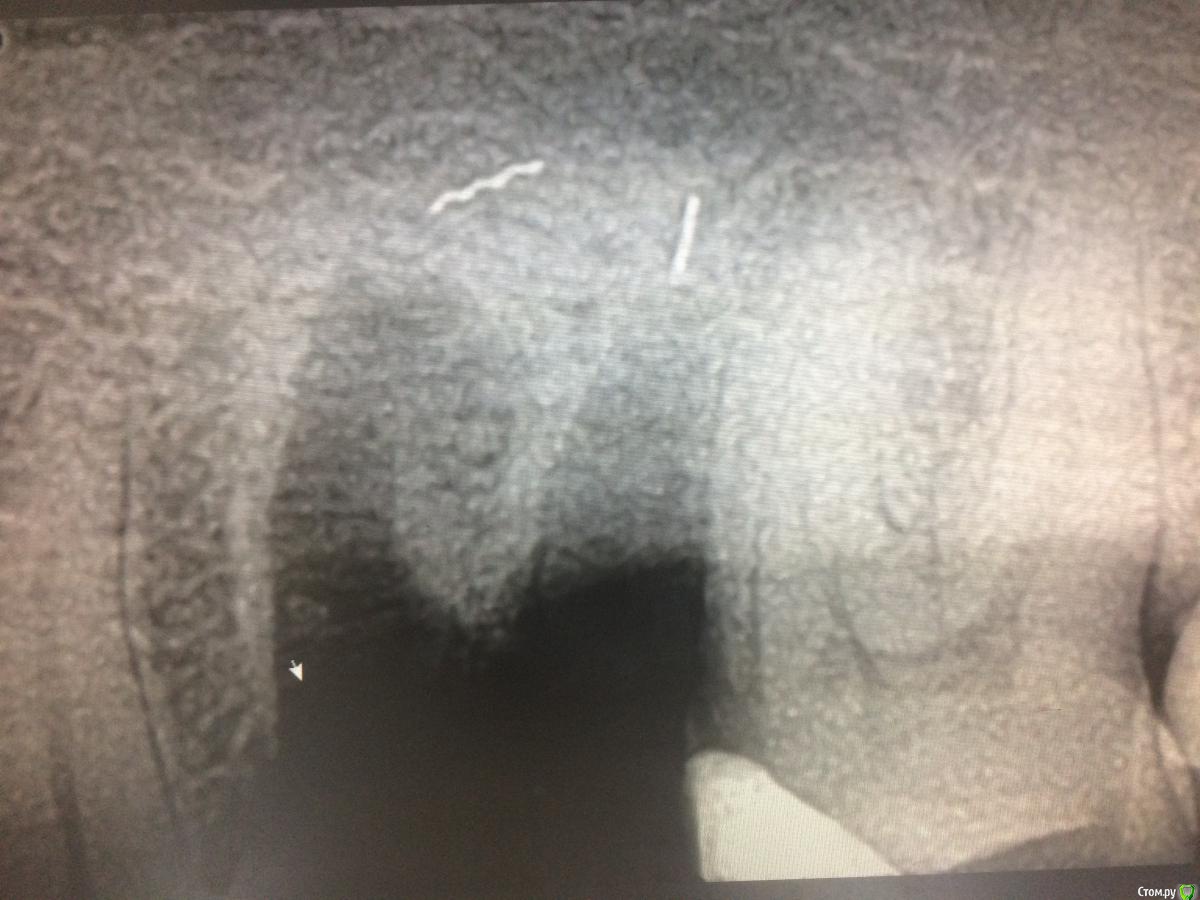

xMeDx Опубликовано 30 января, 2019 Поделиться Опубликовано 30 января, 2019 (изменено) Здравствуйте.Пришла пациентка на удаление .Сделали снимки .В дистальном корне на снимке 4.6 инструмент.Удалил и обнаружил после удаления инструмент ещё и за апексом язычного .Работаю пол года.Подскажите как удалить инструменты и стоит ли их удалять если пациентка с таким зубом проходила 15 лет ? Изменено 30 января, 2019 пользователем xMeDx Ссылка на комментарий

Дмитрий М Опубликовано 31 января, 2019 Поделиться Опубликовано 31 января, 2019 делайте КЛКТ, там и видно будет как лучше поступать Ссылка на комментарий